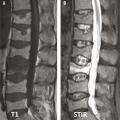

Une première explication à la négativité de ces essais randomisés est l’importance de l’effet placebo sur une douleur d’une procédure factice dont la mise en scène est en tout point similaire à celle d’une véritable intervention. Ces deux essais contrôlés ont aussi un certain nombre de limites méthodologiques. Une proportion importante des patients avait des douleurs depuis plus de 3 mois : inclure des patients jusqu’à un an après la survenue de leur fracture vertébrale ostéoporotique va à l’encontre du bon sens clinique, d’autant que les garanties apportées par les auteurs sur la relation entre la fracture et les douleurs persistantes sont insuffisantes. Ces essais comportent aussi des limites d’ordre technique : le trocart était de faible calibre, l’abord unipédiculaire et par conséquent la quantité de ciment injectée dans les corps vertébraux relativement faible. Deux limites majeures de ces études sont à souligner. L’intensité douloureuse requise pour pouvoir inclure ces patients était très modérée puisque le seuil minimal sur une échelle d’auto-évaluation (échelle visuelle analogique [EVA]) requis comme critère d’inclusion n’était que de 3 ou 4 sur 10,4, 3 ce qui est défavorable à la mise en évidence de tout effet thérapeutique. Enfin et surtout, les patients étaient inclus sans s’être formellement assurés de la présence d’un signal d’œdème médullaire en imagerie par résonance magnétique (IRM), critère majeur de définition du caractère récent d’une fracture vertébrale ostéoporotique et de sa responsabilité dans les douleurs vertébrales (fig. 3).